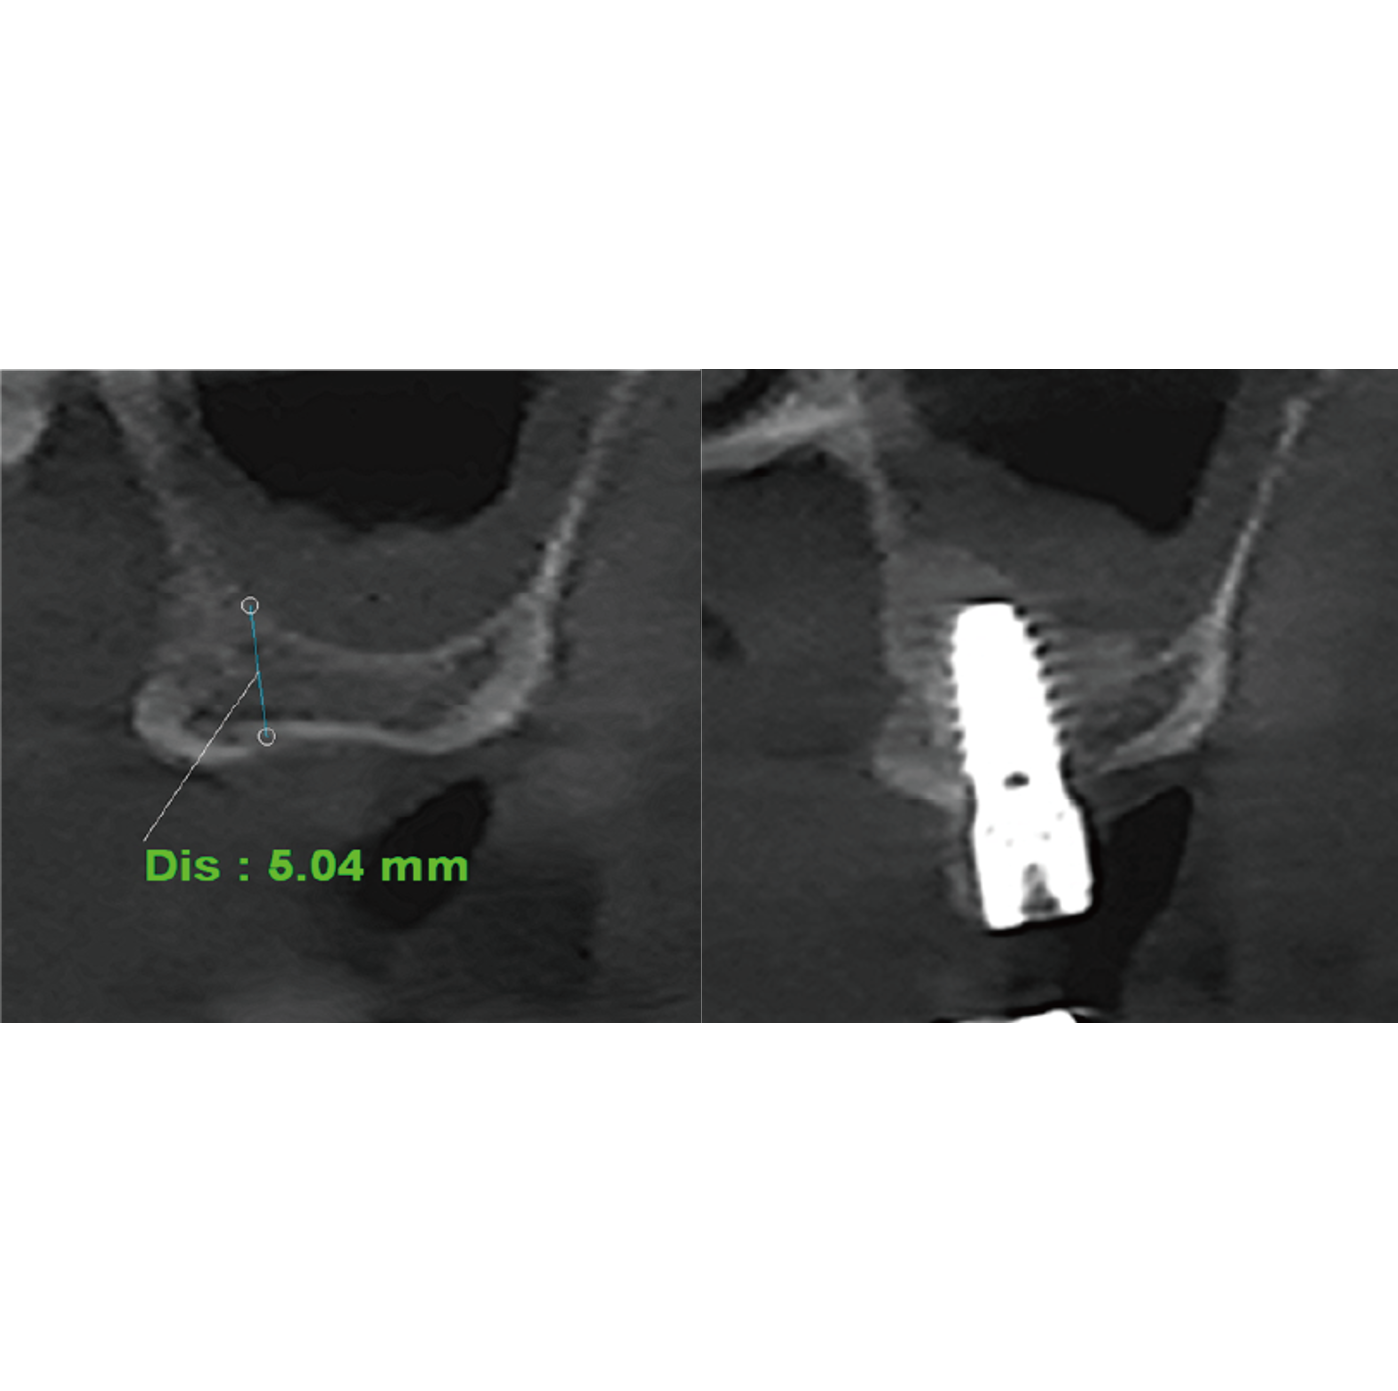

Bicortical FixationThe fastest and simplest approach for cases with remaining bone height of 5 mm or more.

Autogenous bone chips generated by the compaction drill gently elevate the membrane by 1–2 mm.

Stable bicortical anchorage can be achieved without additional graft materials. -